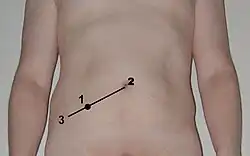

- Die Palpation des Unterbauchs, McBurney-Punkt, Lanz-Punkt, retrogrades Darmausstreichen in Richtung Appendix (sog. Rovsing-Zeichen, diese Untersuchung ist gefährlich und sollte nicht durchgeführt werden)

Grundsätzlich bleibt die Operation indiziert, wenn eine akute Appendizitis, die eine bedrohliche Bauchfellentzündung (Peritonitis) verursachen kann,[20] nicht mit hinreichender Sicherheit auszuschließen ist. Das Risiko der negativen Appendektomien ist geringer anzusetzen als das Risiko der akuten Appendizitis. Bei bis zu 28 % der Patienten wird bei der Operation eine Perforation der Appendix festgestellt, die mit einer Letalität (Sterblichkeit) von ca. 10 % einhergeht (beim Auftreten einer diffusen Peritonitis bis zu 30 %).[21] Dabei sollte möglichst früh (innerhalb von etwa 48 Stunden) operiert werden. Die Appendektomie kann offen chirurgisch durch den sogenannten Unterbauchwechselschnitt (sog. Laparatomie) durchgeführt werden oder laparoskopisch mit Hilfe einer in die Bauchhöhle eingeführten Kamera und weiteren Arbeitszugängen (sog. minimalinvasive Laparoskopie bzw. „Schlüssellochchirurgie“).

Eine bei perforierter Wurmfortsatzentzündung, wie sie seit dem 18. Jahrhundert bekannt ist (1759 Mestivier, Lamotte 1766[33]), durchgeführte Entfernung der Appendix vermiformis erfolgte auch 1887 durch George Thomas Morton.[34] Einer der ersten deutschen Chirurgen, der sich für die operative Entfernung des entzündeten Wurmfortsatzes einsetzte, war der gebürtige Mecklenburger Bernhard Riedel (seit 1888 Ordinarius und Direktor der Chirurgischen Klinik in Jena). Gleichzeitig mit dem Amerikaner Charles McBurney erarbeitete Riedel den Wechselschnitt als Operationstechnik. McBurney, der ebenfalls die Frühoperation bei Appendizitis propagierte, veröffentlichte 1889 vor der New York Surgical Society seinen klassischen Bericht über das frühzeitige operative Eingreifen, welches durch John Murphy (1857–1916) populär gemacht wurde und sich ab etwa 1910 auch in Europa allgemein durchsetzte.[34][35] McBurney beschrieb die Stelle des stärksten Schmerzes im rechten Unterbauch, die seither als McBurney-Punkt bekannt ist. Nach den ersten chirurgischen Erfolgen bei der Blinddarmentzündung wurde die Krankheit für mehrere Jahrzehnte eine rein chirurgische Angelegenheit. Der Chirurg diagnostizierte und operierte sie. Das führte zu einer relativ hohen Zahl von Blinddarmoperationen. Ein Meilenstein in der chirurgischen Technik war die Einführung und Verbreitung der laparoskopischen Appendektomie in den Jahren 1980 bis 1990.